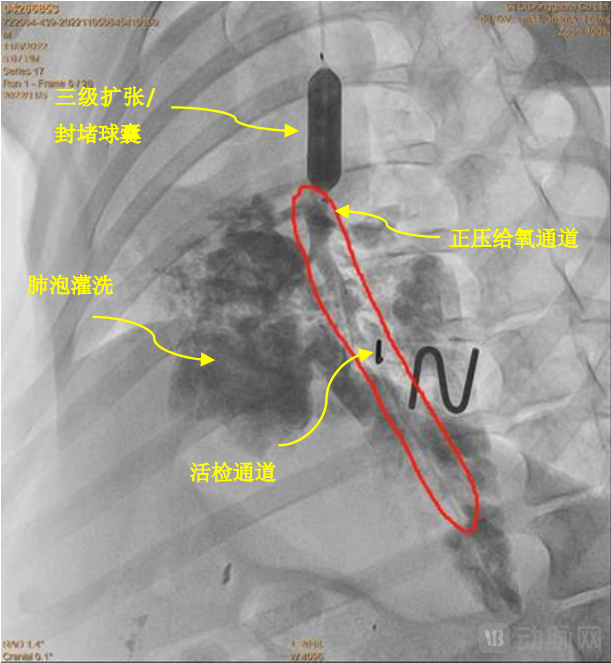

其中,第一个通道是三级扩张球囊,三级扩张球囊的主要功能是保持呼吸道畅通。第二个通道用作排痰,可以将患者肺部的异物排出,同时可以利用该通道输入生理盐水或药品冲洗患者肺部。第三个通道的作用是给氧。第四个通道位于三通道中间,可使光纤内窥镜通过,便于医生了解患者肺部的情况,并可利用设备取出样本进行观察。

第二,呼吸道急救多功能球囊扩张导管可实现细小支气管及肺泡层次的灌洗与排痰。将抽吸通道与吸痰机连接,可吸出肺部细小支气管炎症区域内的分泌物,也可利用该通道反复冲洗炎症区域,起到局部消炎作用。同时,封堵球囊也能阻断呼吸机对炎症部位的机械挤压,避免炎症向深层的堆积。

第三,呼吸道急救多功能球囊扩张导管可实现肺内正压给氧。将给氧通道与氧气机连接,当球囊打开时,球囊封堵远端支气管形成一密闭高压氧仓,远端氧气开口直接对炎症区域的组织持续正压给氧,近端开口则对其他区域的肺泡直接供氧。

第四,呼吸道急救多功能球囊扩张导管可实现细小支气管及肺泡组织的活检。活检通道位于导管的中间,可使光纤内窥镜、导丝或活检钳轻松通过,便于医生了解患者肺部的情况,并可利用设备取出样本进行详细观察。